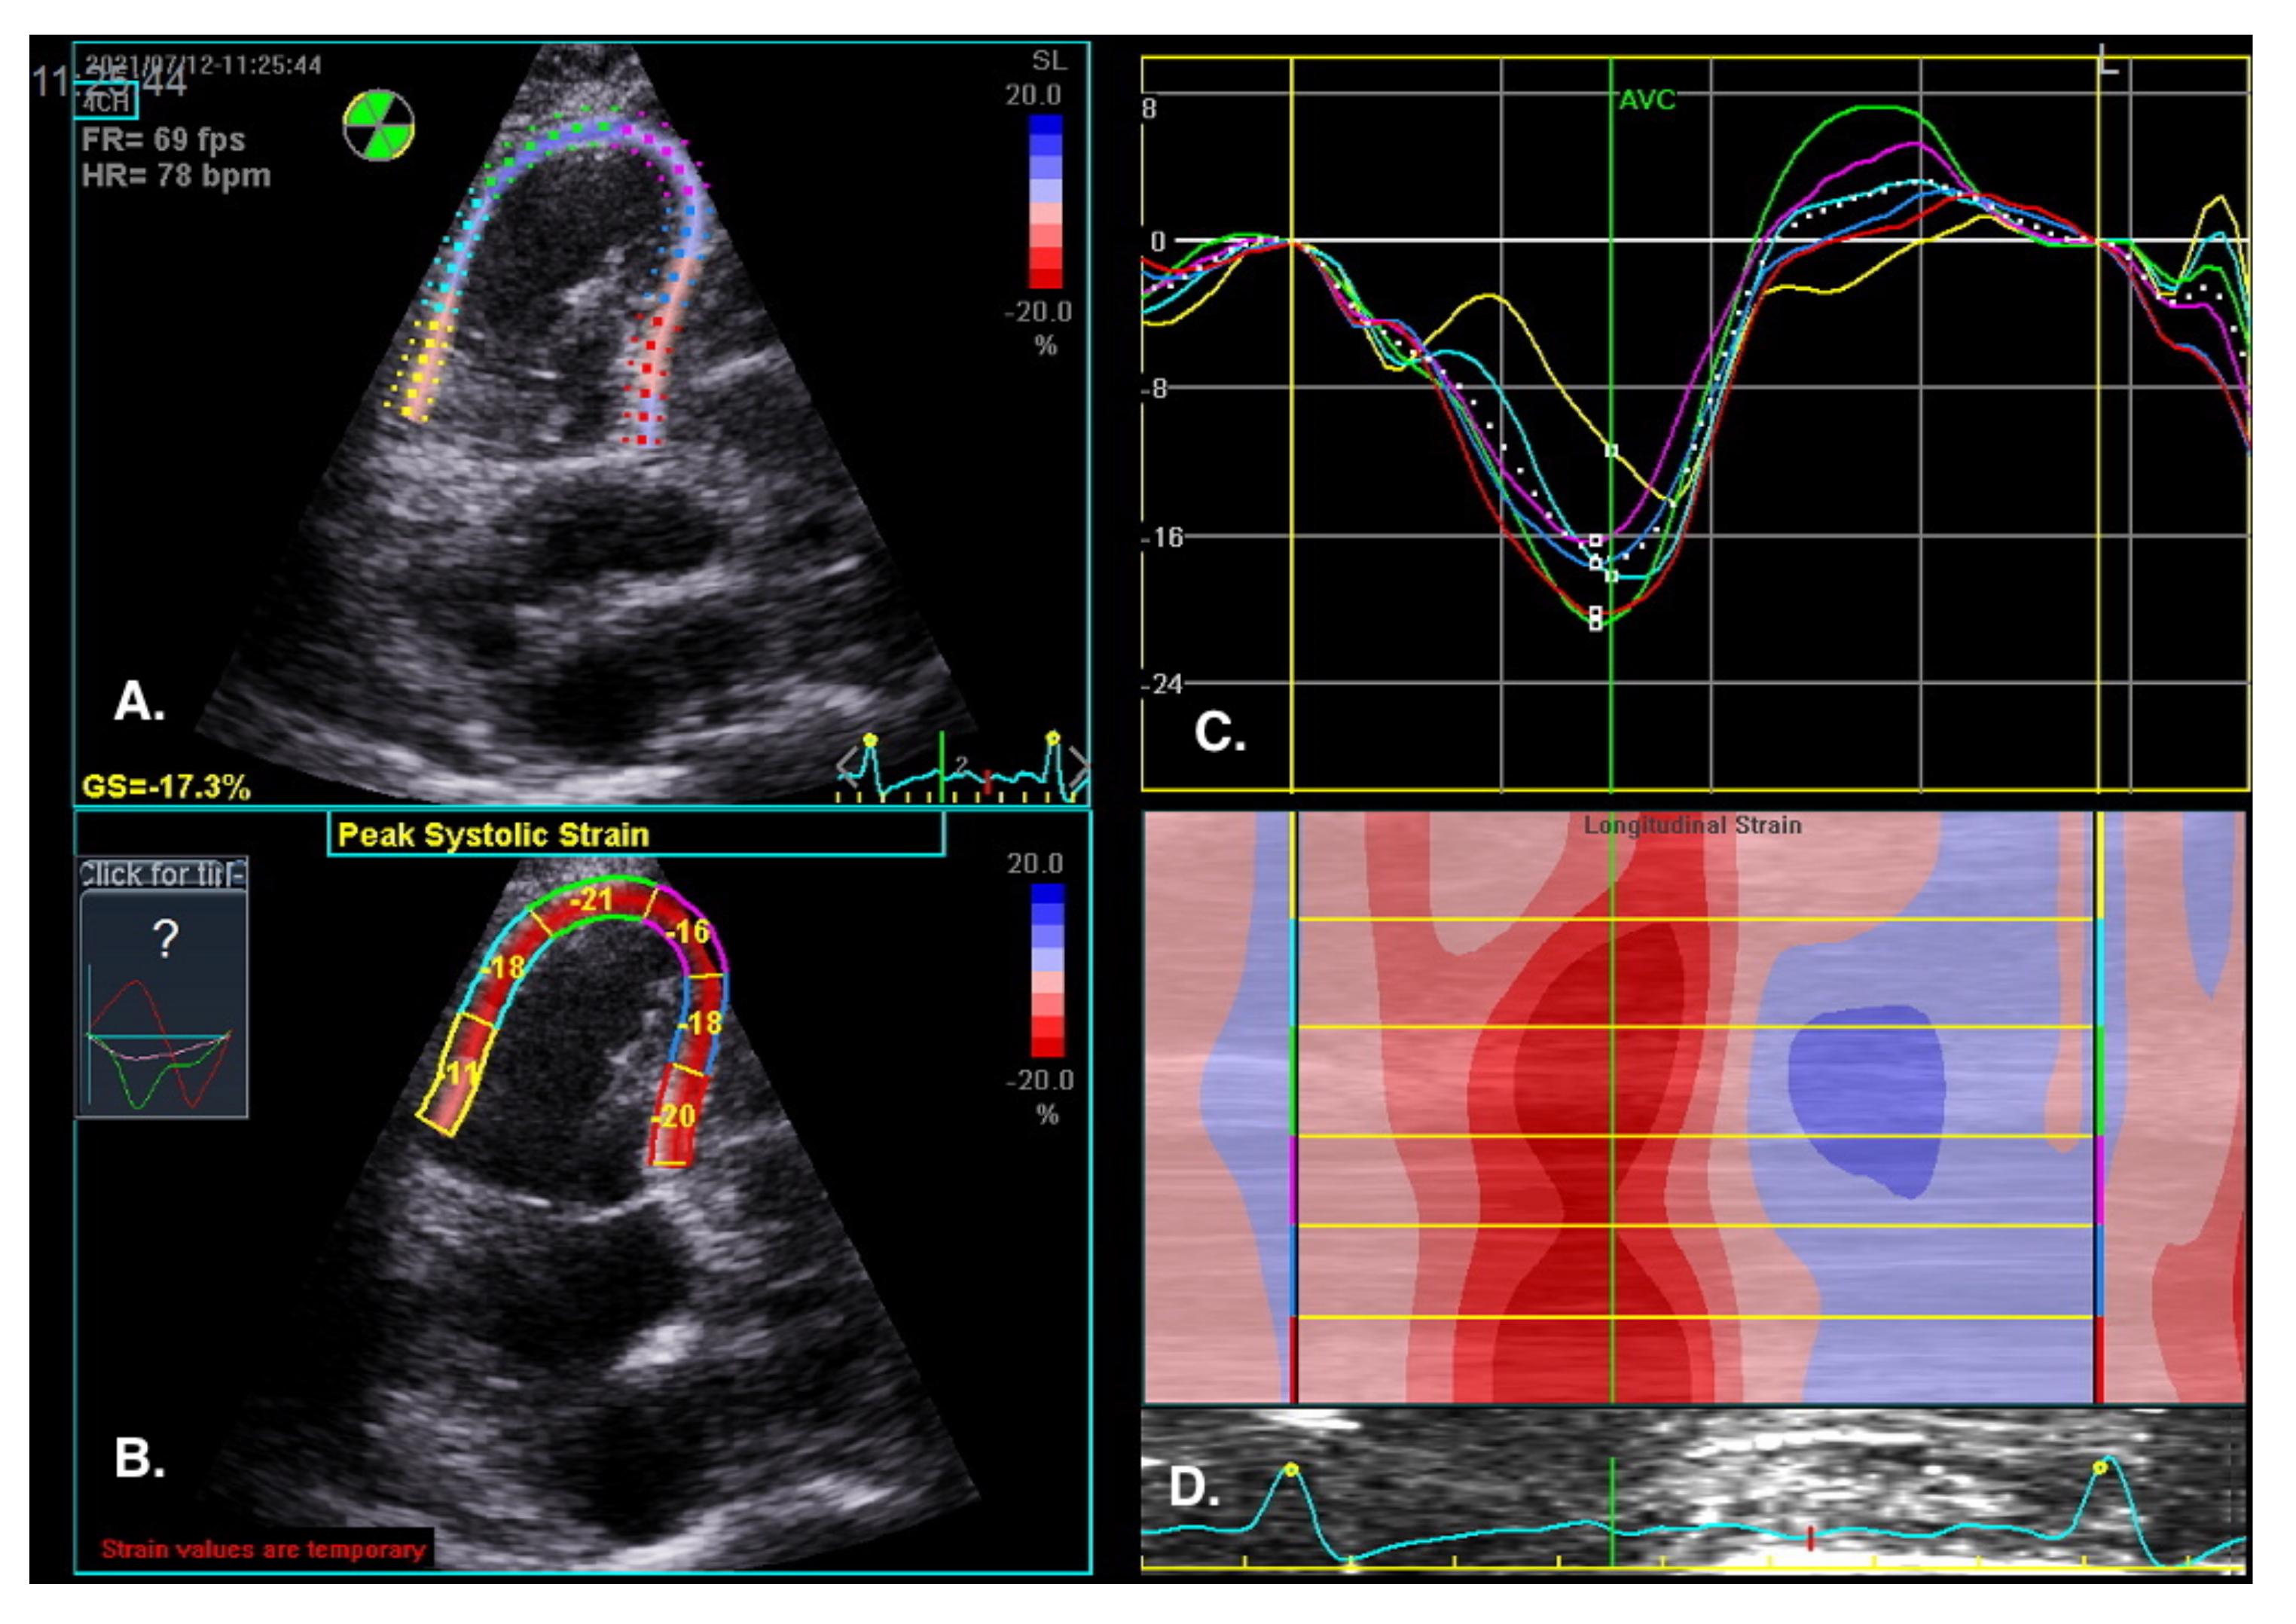

The visual assessment of myocardial contractility is very subjective and requires considerable experience from the investigator. New techniques can objectify the assessment of the segmental and global RV systolic function [59]. Myocardial strain is the percentage change in the distance between two points in the heart muscle during the cardiac cycle. In contrast, the strain rate is the rate of change in the distance between these points and is expressed in units of s−1. Initially, strain and strain rate were evaluated using TDI [60]. Currently, 2D strain and speckle tracking techniques are used, which involve automatic tracking of myocardial acoustic markers in standard echocardiographic images [61]. It allows the analysis of strain and strain rate in different directions (Figure 10). A newer and more precise technique for the assessment of strain and strain rate is three-dimensional echocardiography. This technology is currently under intensive development; however, reports of this method′s high efficacy in assessing the prognosis in patients with PAH are already available [62].

Figure 10.

RV regional myocardial contractility (longitudinal strain) assessment by speckle tracking imaging. RV-focused view, 4CH. (A) Tracked apical loop with colour coding of the RV free wall and interventricular septum myocardial segments. (B) Regional end-systolic strain. (C) Segmental strain curves and segmental strain values displayed during the cardiac cycle. Global longitudinal strain at peak strain is visualized with the global strain curve (white dotted line). (D) M-mode representation of peak systolic strain. Blue colour- myocardial lengthening, red colour- myocardial shortening.

The normal RV systolic strain values in healthy subjects amount to: RV global strain −24.5 ± 3.8 and RV free wall strain −28.5 ± 4.8 [63].

Sachdev et al. demonstrated that RV longitudinal peak systolic strain (−15 ± 5%) and strain rate (−0.80 ± 0.29 s) are significantly reduced in patients with PAH. Moreover, RV-free wall strain was also reduced in the study group, which was associated with a decreased 1-year survival [65]. Other studies show that right atrial strain may also have a diagnostic value in patients with PAH [66].

A: Tracked apical loop with color coding of the RV-free wall and interventricular septum myocardial segments. B: Regional end-systolic strain. C: Segmental strain curves and segmental strain values displayed during the cardiac cycle. Global longitudinal strain at peak strain is visualized with the global strain curve (white dotted line). D: M-mode representation of peak systolic strain. The normal RV systolic strain values in healthy subjects amount to an RV global strain −24.5 ± 3.8 and RV free wall strain −28.5 ± 4.8 [63].